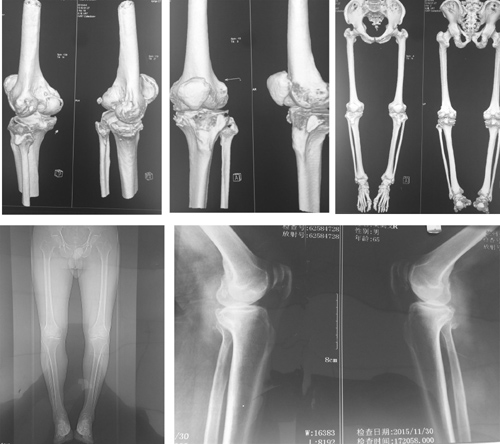

骨一科成功完成一例人工膝关节置换术

近日,骨一科成功完成一例人工膝关节置换术。目前,患者恢复良好。

术前影像图

术后查房图